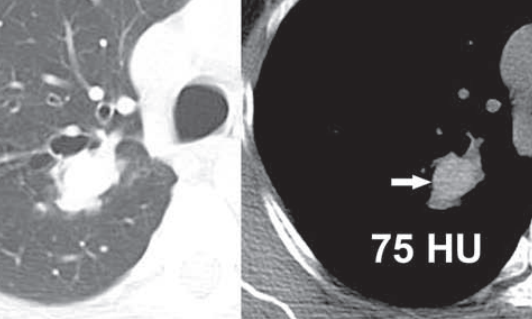

- granulomatose broncho-centriques (impaction de mucus dense >70 HU, 30% des cas)

Finger in glove, bronchiectasies

impactions avec mucus dense

Patient avec ABPA récurrent